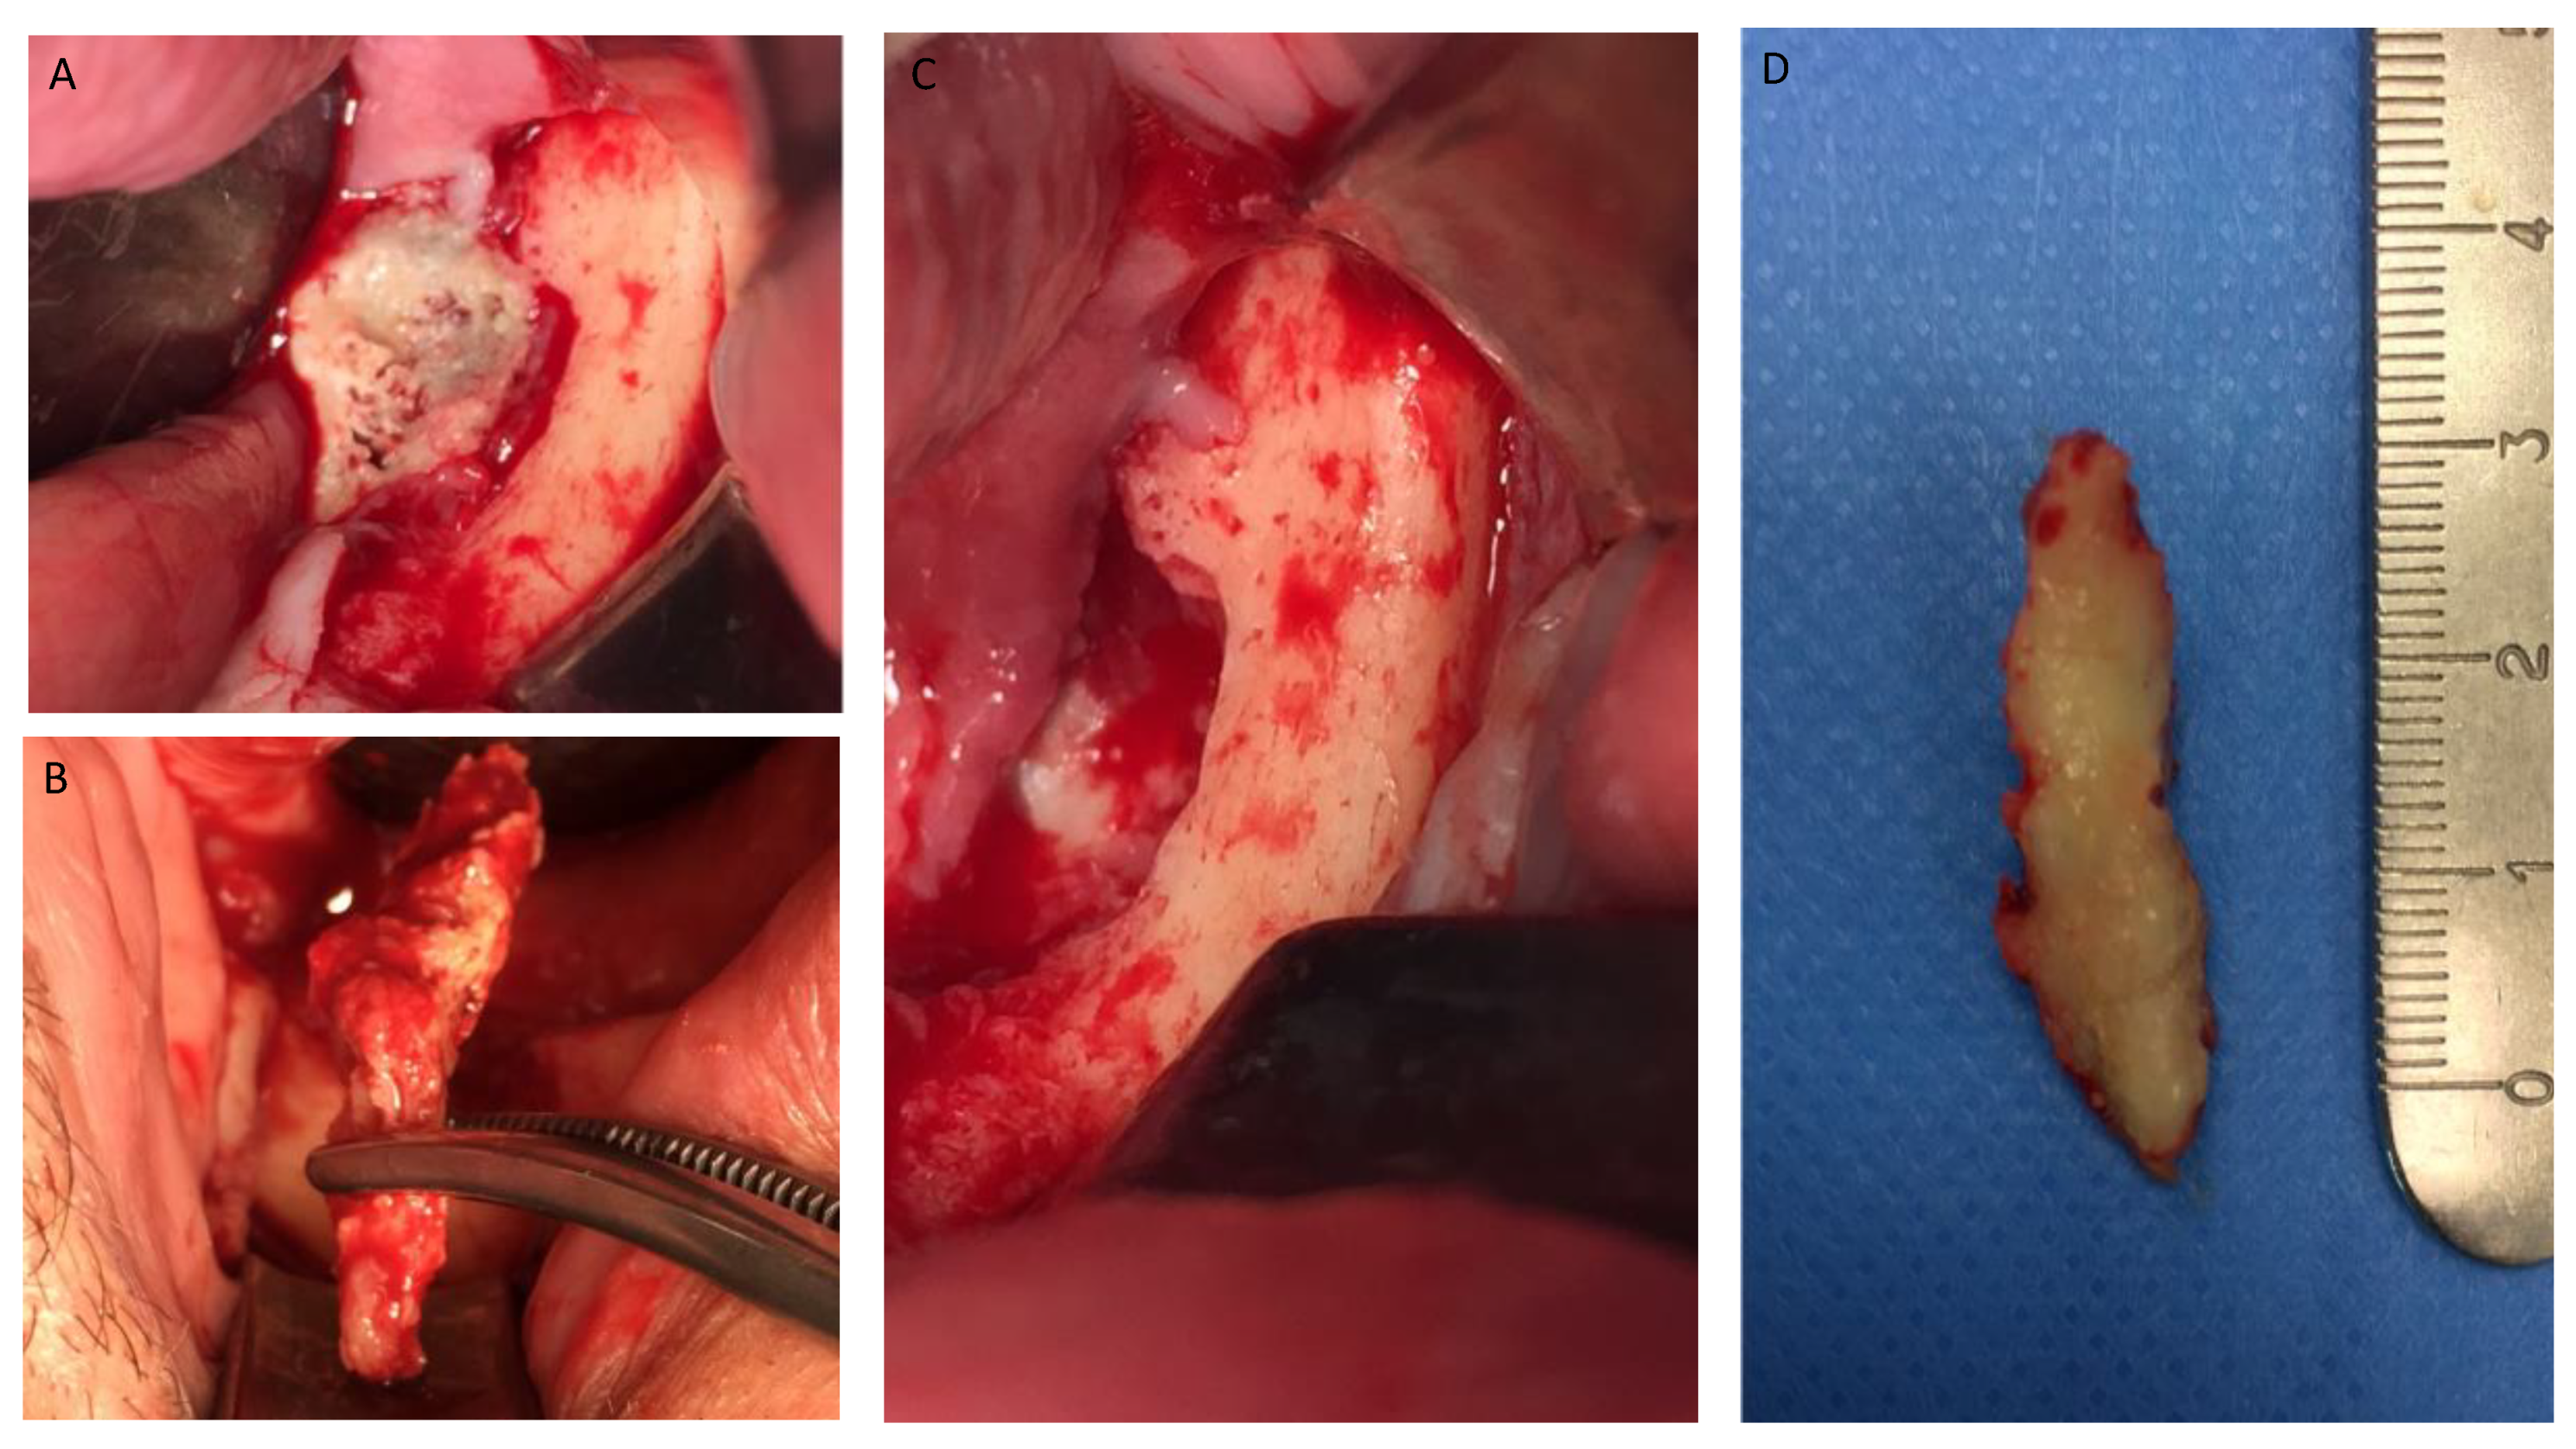

Figure 1, Figure 2, Figure 3, Figure 4, Figure 5, Figure 6 and Figure 7 show the progress of treatment in one of the patients of the test group. In Figure 3 reduction of the medullar space is visible, that may create a chronic ischemic area susceptible to necrosis.

Figure 4.

(A–D) Intra-operative view showing operation steps and resected osteonecrotic tissue from the right side of the mandible. After pharmacological preparation with pentoxifylline and tocopherol, the cleavage plane created by the reactive granulation tissue can be clearly seen which tends to separate the necrotic tissue from the healthy bone. Sequestrectomy was made using an osteotome to obtain the necrotic specimen. After the debridement, the bottom of the surgical area was bleeding properly, which creates a favorable environment for healing.

Figure 5.

(A–D) Intra-operative view showing sequestrectomy operation and resected osteonecrotic tissue from the left side of the mandible.